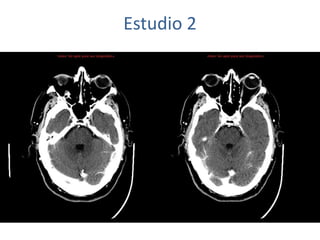

Estudio 2

• Estudio sin y con contraste, con reconstrucciones sagitales y coronales

del estudio con contraste.

Se observa una lesión ocupante de espacio en lóbulo frontal derecho que

presenta un tamaño de 18 x 32 x 22 mm (cc x ap x tr), bilobulada, no del

todo bien delimitada, con realce en anillo irregular, con hipocaptación

central, probablemente por necrosis, y asociada a un extenso edema

vasogénico con efecto masa tanto sobre los surcos de la convexidad

como sobre la cisterna insular, el sistema ventricular y la línea media,

esta última con un desplazamiento de 5 mm a la altura del septo

interventricular.

No se aprecian otras lesiones focales intra o extraaxiales de significación

patológica.

Habría que considerar como primera posibilidad que se tratase de una

lesión metastásica, por bien un tumor primario, aunque no se puede

descartar otras opciones, sin imprescindible correlación con la clínica y

con sus antecedentes.